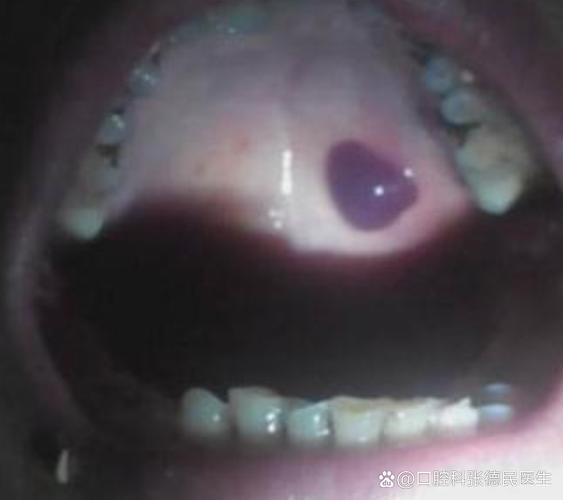

核心观点:口腔内壁黑血泡与艾滋病没有直接的必然联系。

绝大多数情况下,口腔内的黑血泡是由其他更常见、更良性的原因引起的,艾滋病病毒(HIV)感染后,口腔出现的症状通常是特定的、并且是晚期的表现,而不是一个孤立的、突然出现的黑血泡。

口腔黏膜下的黑血泡,在医学上通常被称为“血疱”(Hematoma),它是由于毛细血管破裂,血液渗出到黏膜下层形成的,导致其破裂的原因有很多:

- 卡波西肉瘤:一种与HIV相关的癌症,表现为口腔内(特别是上颚)出现紫红色、蓝色或褐色的斑块、结节或肿块,质地较硬,不是血泡。

- 黑血泡:通常是急性的,由创伤引起,会像身体其他部位的淤青一样,几天内慢慢变色、吸收、消失。